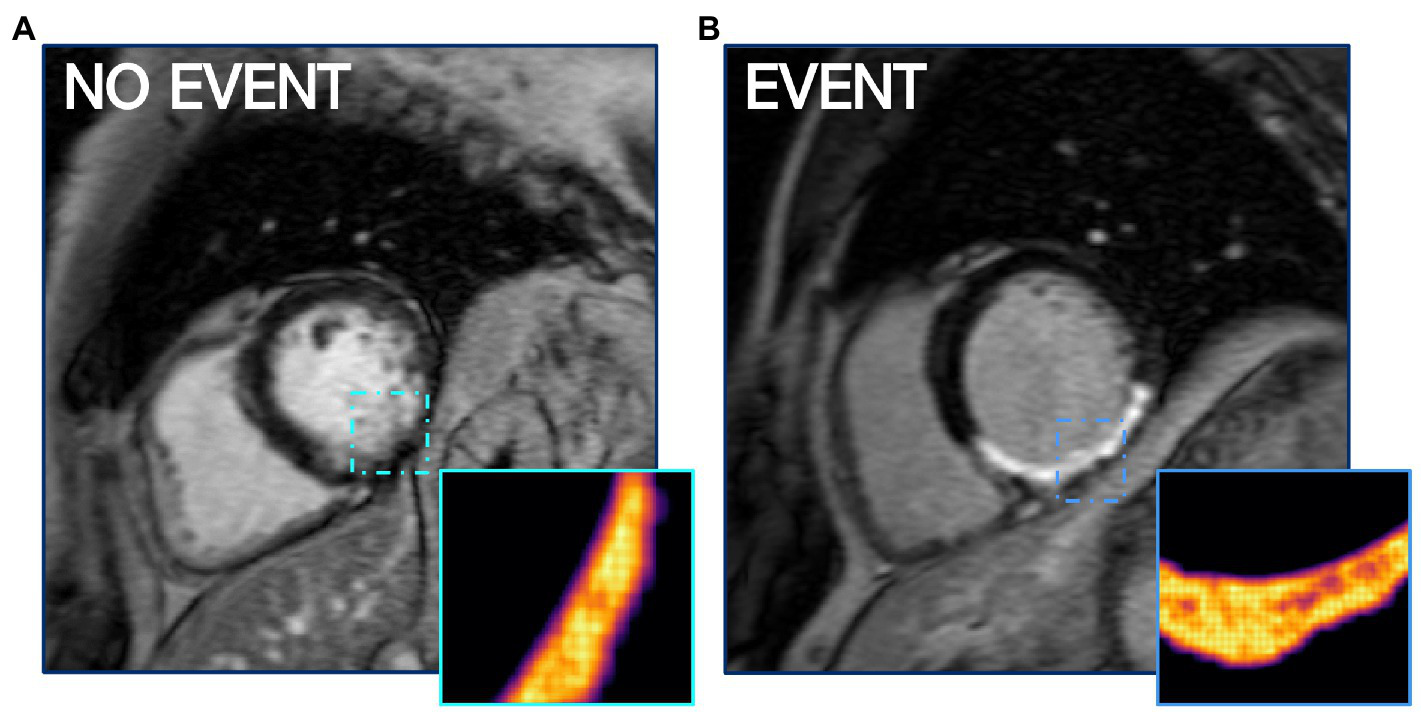

Entropy describes the level of disorder within the region of a scar. This metric was included in all 4 best performing models as either PIZ entropy or combined entropy (Table 4), and suggests that patients with higher arrhythmic risk have a more complicated composition of viable myocytes and fibrotic components in the PIZ region (Figure 4). The strength of PIZ entropy is in identifying subtle tissue characteristics by filtering out image noise and accentuating key features. Entropy has previously been shown to associate with ventricular arrhythmia (13, 16) and is potentially more reproducible than other measures of tissue characterization including T1 mapping (13).

Figure 4

PIZ Entropy is significantly (p ≤ 0.05) higher in patients who have MAE, as seen in (B) compared to a non-event patient LGE CMR shown in (A). Images depict entropy via FWHM quantification.